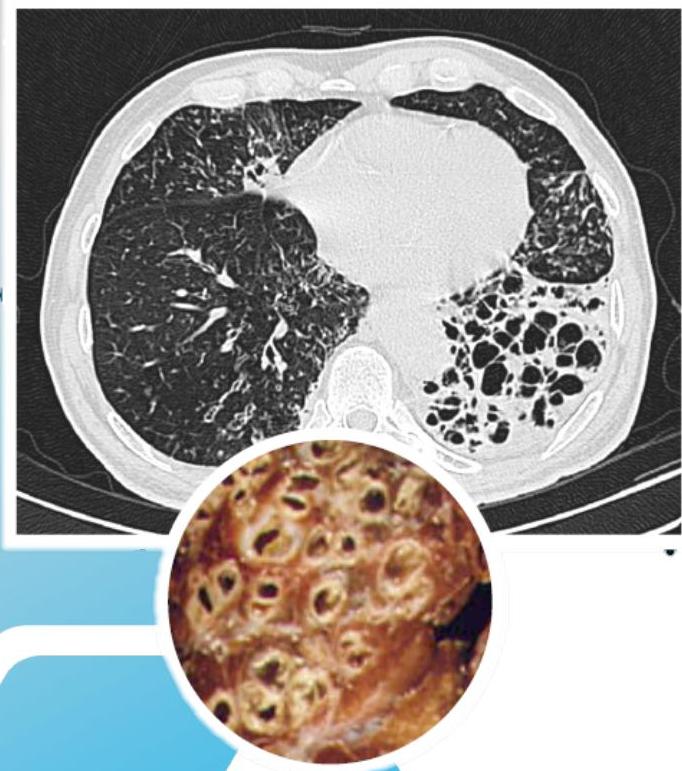

- ☐ Thin-section HRCT scanning: is the gold standard, with excellent sensitivity and specificity.

- ☐ Chest X-ray: increase in size and loss of bronchovascular markings, crowding of bronchi, and loss of lung volume. Severe case: Honeycombing.

Radiographic Findings (Chest X-ray)

Conglomerating cysts of varying size and wall thickness. “Honeycomb” sign.

CT Scan Findings

Cylindrical

Saccular/Varicoid

Cystic

Signet Ring Appearance

CT scan showing bronchiectasis. Note the dilated bronchi with thickened wall, which are larger than adjacent arteries, giving a signet ring appearance.